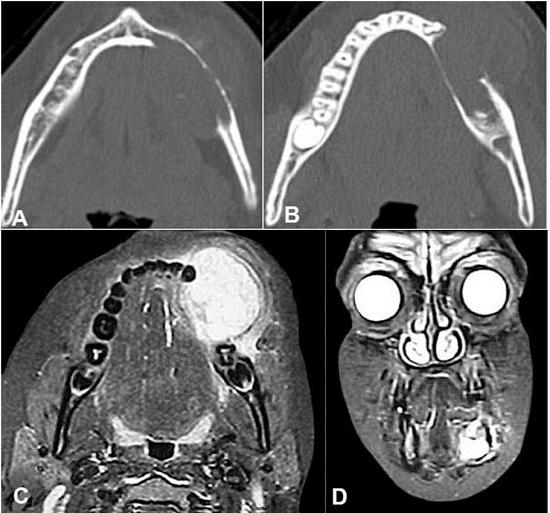

Computed tomography revealed the rupture of the lingual and buccal cortical bone. The tumor was a solid lesion with a density similar to that of the soft tissues (Figure 2A and 2B). Similarly, magnetic resonance imaging (MRI) presented the involvement of the buccal and lingual lesion (Figure 2C and 2D).